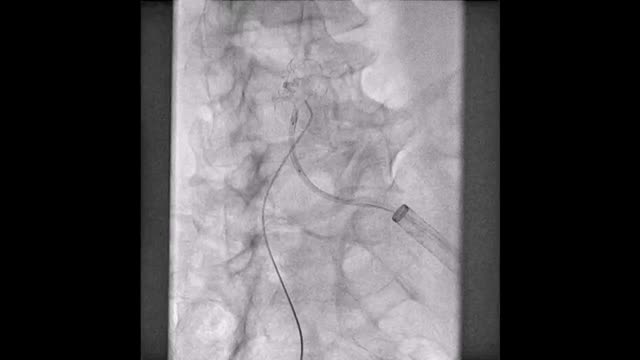

El paciente se traslada a la sala de hemodinamia donde se intenta la extracción del dispositivo. Se utilizan diferentes catéteres lazo de 10, 25 y 30 mm, así como lazos de fabricación con guías largas y cortas intentando movilizar el dispositivo desde diferentes accesos vasculares (acceso bifemoral 6 y 18 Fr y radial 6 Fr) (figuras de la 1 a la 4). Se produce como complicación disección de aorta abdominal con extensión a arteria ilíaca común derecha (figuras 5 y 6) y pérdida total del flujo en extremidad inferior ipsilateral con signos y síntomas de isquemia arterial aguda, por lo que el paciente es trasladado de forma urgente al quirófano de angiología y cirugía vascular. Se realiza disección de aorta abdominal infrarrenal vía laparotomía media con aortotomía longitudinal en el lugar de la localización del cuerpo extraño visualizándose el dispositivo migrado anclado a la íntima-media de la pared arterial. Se procede a su extracción y posteriormente se realiza cierre de aortotomía con parche de pericardio bovino fijando la disección y corrigiendo así el defecto (figuras de la 7 a la 9). El paciente sale de quirófano con pulso pedio bilateral y excelente perfusión distal.